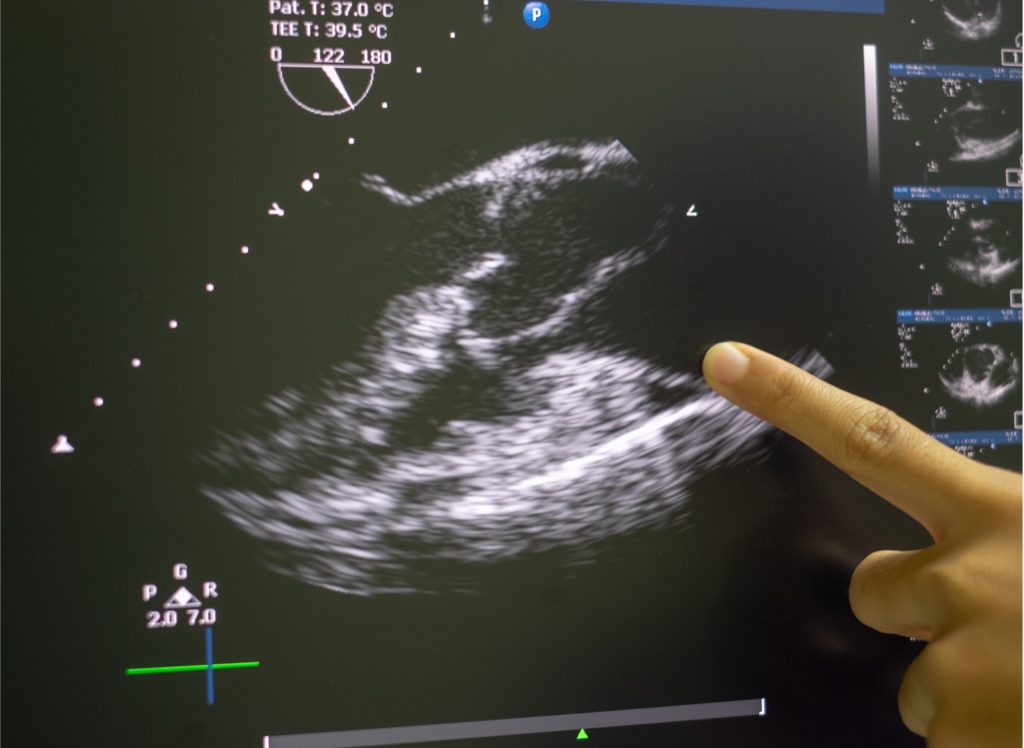

Dr. Jonathan Sen MBBS, PhD, BHSc(Hons), FRACP blends clinical experience with the latest research to deliver thorough cardiac care for each patient. He specialises in the prevention and treatment of cancer therapy‑related cardiac toxicity, in advanced heart valve evaluation including multimodality imaging, and heart failure management .

Offer a wide range of advanced heart imaging tests